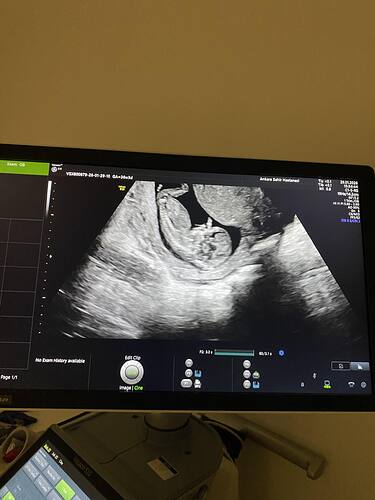

Kese yuvarlak bence kız erkek olsaydı fasulye gibi şekilli olurdu benim oglumda doktor 6 haftalıkken senin olgun olur fasulyen var demişti buda Kısmet aetık

Hayır canım fark etmemiştim seninkini ama kese şekline bakılırsa erkeğe benziyor seninki benim bebişin de kese benzerdi erkek bebek bekliyoruz![]()